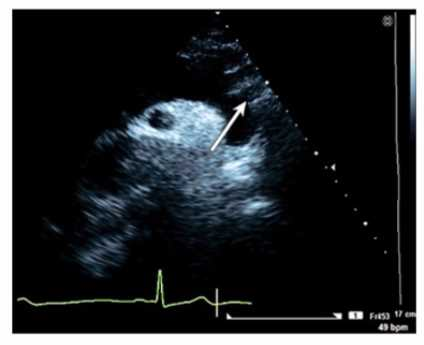

Which congenital abnormality is most consistent with the findings in this video?

The video shows an apical four-chamber or subcostal echocardiographic view demonstrating a markedly enlarged right atrium with atrialization of part of the right ventricle, displacement of the tricuspid valve septal leaflet downward into the RV cavity, and severe tricuspid regurgitation. These findings are hallmark features of Ebstein anomaly, a congenital malformation of the tricuspid valve causing apical displacement of the septal and posterior leaflets.

Patent foramen ovale and ventricular septal defects have different echocardiographic features without tricuspid leaflet displacement. Eisenmenger syndrome refers to advanced pulmonary hypertension due to shunts but is not a specific congenital structural abnormality.